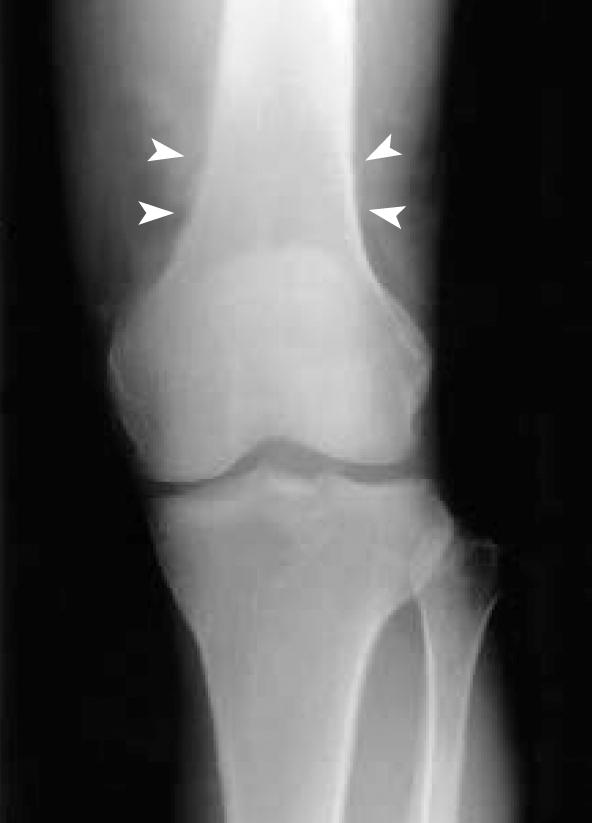

Epithelioid hemangioendothelioma is a rare vascular tumor, which occurs in the lung, liver, bone, and soft tissue. Hypertrophic osteoarthropathy is a syndrome characterized by subperiosteal new bone formation, joint effusion and clubbing, and may be associated with cyanotic heart disease, chronic pulmonary disease, liver disease, and other miscellaneous diseases. The activation of endothelium and platelets has been suggested to be involved in the development of hypertrophic osteoarthropathy. We report a rare case of hypertrophic osteoarthropathy, which developed in association with hepatic epithelioid hemangioendothelioma with pulmonary metastasis. We also discuss the role of vascular endothelial growth factor in its pathogenesis.

上皮样血管内皮瘤是一种罕见的血管肿瘤,可发生于肺、肝、骨和软组织。肥大性骨关节病是一种以骨膜下新骨形成、关节积液和杵状指为特征的综合征,可能与紫绀型心脏病、慢性肺部疾病、肝脏疾病及其他杂病有关。内皮细胞和血小板的激活被认为与肥大性骨关节病的发生有关。我们报告一例罕见的肥大性骨关节病病例,其与肝上皮样血管内皮瘤伴肺转移相关。我们还讨论了血管内皮生长因子在其发病机制中的作用。